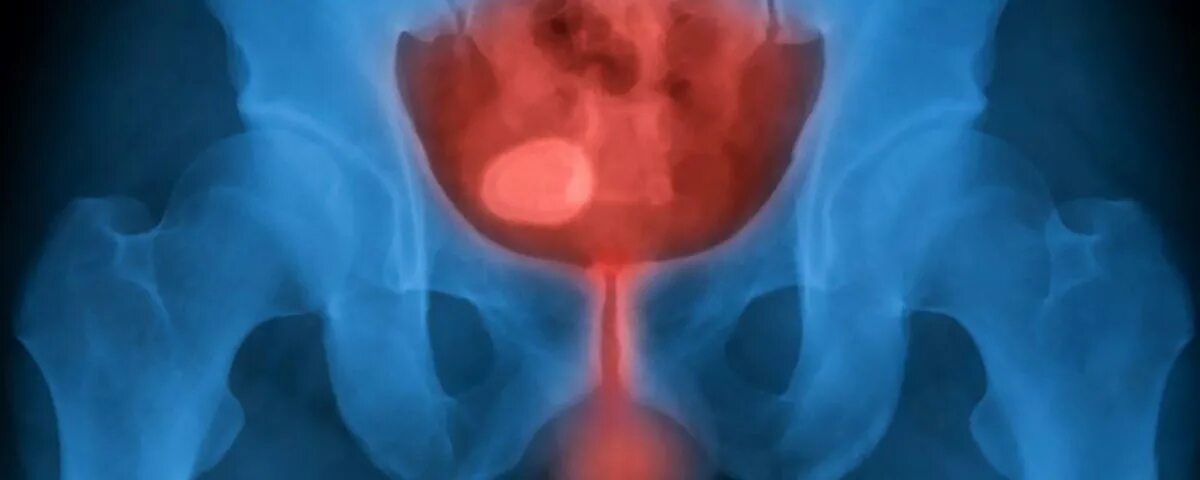

Резь в мочеиспускательном канале